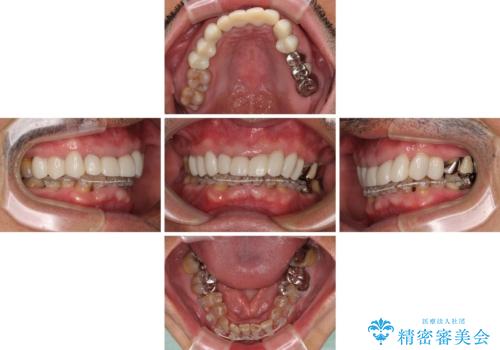

上下ともに前歯のセラミッククラウンによる補綴治療を希望されていましたが、下顎前歯は叢生が強いため、補綴治療前に部分矯正を行って歯列を整えた上で、補綴治療を行うこととしました。

臼歯部には歯周ポケットのある箇所が散見されましたが、まずは前歯を治療したいとのことで、治療を進めました。

ディープバイトにより臼歯部に負担のかかる咬合であったので、補綴治療後には、矯正治療の後戻り防止もかねて、睡眠時にマウスピースを装着するように指示しました。